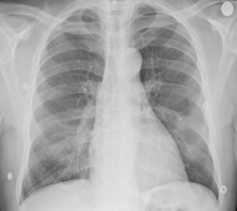

Se recurre a esta técnica de imagen porque, debido a la afectación primaria del sistema respiratorio, la infección por SARS-CoV-2 deja evidencias radiológicas de neumonía visibles bajo los rayos X. Concretamente, la neumonía asociada a la covid-19 produce sombras en los pulmones conocidas como opacidad de vidrio esmerilado. Estas opacidades suelen aparecer con una distribución periférica o posterior, principalmente en los lóbulos inferiores y con menos frecuencia en el lóbulo medio derecho.

En los dos primeros días de la infección, el 50% de los pacientes de covid-19 ya muestra lesiones pulmonares parenquimatosas, superando el 90% entre los 3 y 5 días. Lo sorprendente es que esto ocurre incluso en pacientes asintomáticos. Por ello, complementar la RT-PCR con una radiografía de tórax mejora la sensibilidad en el diagnóstico, reduciendo significativamente el número de falsos negativos. Es importante porque los falsos negativos son precisamente el talón de Aquiles de la prueba RT-PCR, cuya sensibilidad oscila entre el 70-90%. Otra ventaja importante es que la radiografía está lista en cuestión de minutos.

La única pega al uso de esta técnica es que su despliegue masivo tiene un significativo cuello de botella: la necesidad de radiólogos expertos para interpretar y analizar las imágenes. Adicionalmente, el análisis individual de la radiografía de tórax, tal y como lo conocemos, también adolece de una baja sensibilidad, lo que sugiere la necesidad de herramientas complementarias de análisis computerizado.